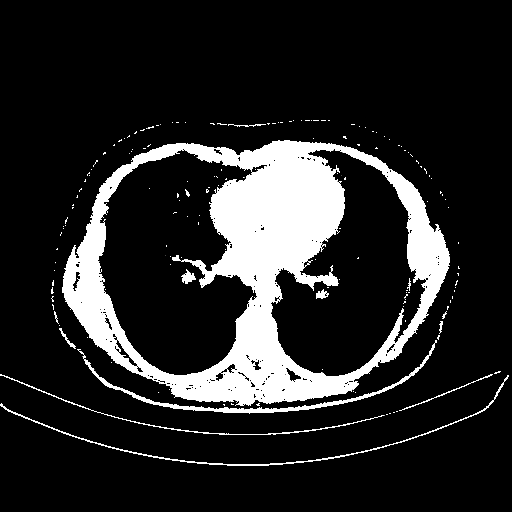

Original VENOUS CT scan

Full window (WL 1023.5, WW 4095 β†’ Low βˆ’1024, High +3071)

Actual HU range: [-1024.0, 3071.0]